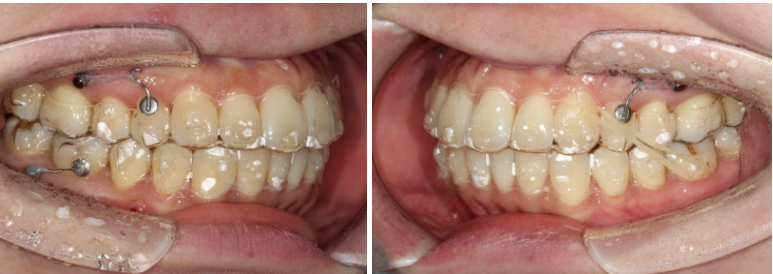

24.11

두번째 세트 장치는 총 33개가 나왔으며 24년 9월부터 25년 4월까지 꼈습니다.

교정용 나사도 추가로 심고 뺏다꼈다 하는 고무줄 처방도 들어갔습니다.

25년 4월, 두번째 세트 장치를 모두 낀 후 모습입니다.

25.04

약간의 중심선 불일치가 아쉬워서 마지막 재제작에 들어갑니다.